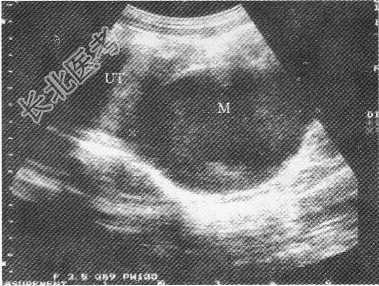

- 单项选择题女性,15岁, 周期性下腹部疼痛伴排尿困难;月经未来潮; 超声检查如图所示,以下最可能的诊断为

E、处女膜闭锁